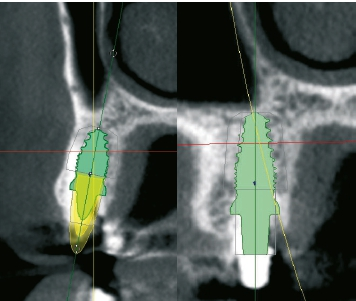

Um einen sinnvollen prothetischen Einschub unter optimaler Nutzung des Knochenangebots gewährleisten zu können, entschied man sich für eine teilnavigierte Aufbereitung des Implantatbetts. Mit der digitalen Planung sollte auch direkt nach der Implantatinsertion Primärstabilität gewährleistet werden, die für eine provisorische Sofortversorgung unerlässlich ist [8]. Als Implantat wurde das im Rahmen einer prospektiven, klinischen Langzeitstudie erprobte yttriumstabilisierte, einteilige Zirkondioxidimplantat ceramic.implant (vitaclinical, Bad Säckingen, Deutschland) ausgewählt, um der Patientin im Langzeitverlauf größtmögliche Sicherheit zu bieten. Das Implantat ist seit fünf Jahren dokumentiert und zeigt hier stabile Knochen- und Weichgewebsverhältnisse. Die Dreijahresdaten wurden bereits publiziert [9].

Um eine dreidimensionale Planung vornehmen zu können, wurde ein DVT erstellt und die Bilddaten wurden in die Planungssoftware 3Shape Implant Studio (3Shape, Kopenhagen, Dänemark) transferiert. Dort konnte die Implantation virtuell vorgenommen und in allen Raumdimensionen optimiert werden. Auf dieser Grundlage wurde eine Bohrschablone zur Teilnavigation hergestellt. Mittlerweile ist auch eine vollnavigierte, hülsenlose Implantation mit dem ceramic. implant möglich, das im Rahmen einer klinischen Studie eine noch präzisere Positionierung als bei den gängigen hülsengeführten Bohrschablonen zeigte [10].